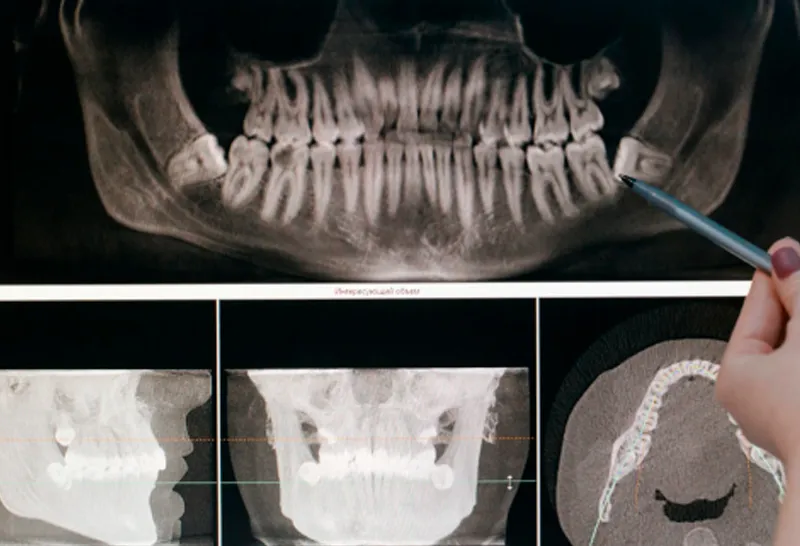

Análise de exames de imagem (ênfase em tomografia)

Exodontias simples e complexas (ênfase em terceiros molares)